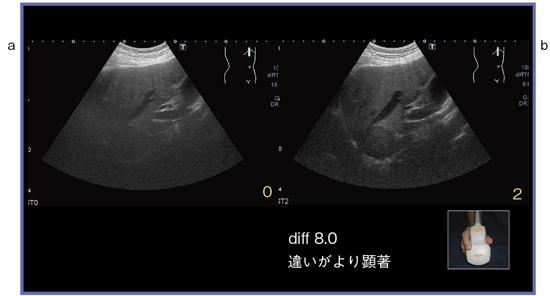

S1に大腸がんの転移性腫瘍(35mm)を認める。図10のBモード画像右下の数字はBeam Enhance Technologyの適用レベルを示す。0(適用なし)〜4の5段階を選択可能である。レベル3,4ではフレームレートが下がる傾向がある。図10は,PVT-674BT/differential6.0のコンベックスプローブによるBeam Enhance Technologyである。適用なし(a)に比べてレベル1(b)と2(c)では,腫瘍の境界がより明瞭に描出され,輪郭不整像を示していることがわかる。また,腫瘍より深部の構造物もより明瞭に描出されている。differential8.0では,適用なし(a)に比べて,レベル2(b)では腫瘍の認識が容易である。明らかな違いを認識することができる(図11)。

図11 症例4のdiff8.0での画像比較